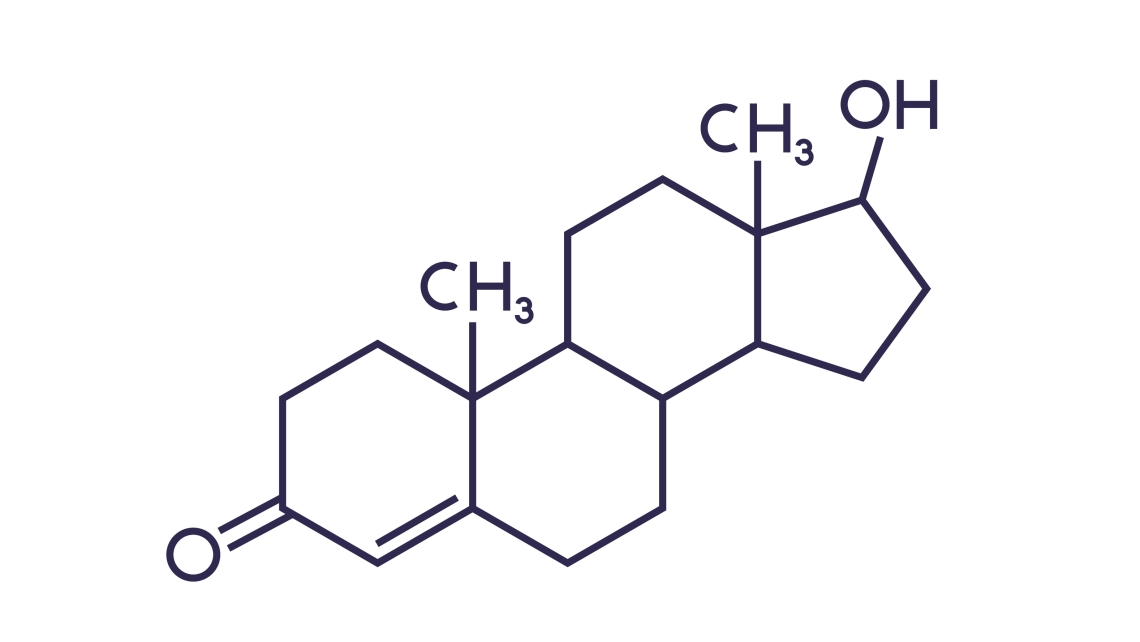

COMPOUNDING

iDEXIS Compounding specialises in scientifically formulated compounds for healthcare providers, with a focus on integrative health, functional medicine, and aesthetic solutions.